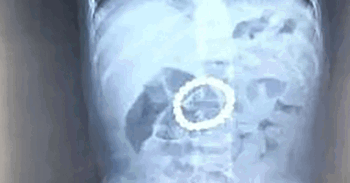

They brought him to their local hospital in Hebei Province, China, where an x-ray revealed a mass of small magnetic beads in his stomach. However, doctors were unable to remove the magnets.

Surgeons at Beijing Childrens Hospital removed a ring of 21 magnetic balls from a toddlers stomach. Photo: Weibo

Image source: Weibo

Doctors concluded the magnetic beads — 21 in total — were in the boy’s stomach for four to five days. During the operation, doctors managed to remove all the magnetic beads, which had already formed a ring inside the toddler’s stomach.